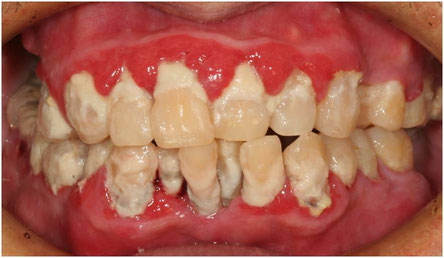

歯石が大量に付着した口腔内。ほとんど歯を磨かないそうです。歯石・歯垢を除去しました。今後、ブラッシングを継続すれば、健康な歯茎に回復します。